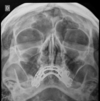

ANALISE A TOMOGRAFIA

Quando vaoms pensar em sinusite fúngica?

Quando temos, além da destruição do osso, presença de calcificações dentro da opacidade